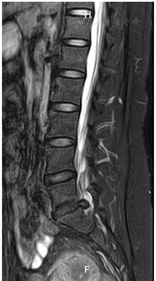

辅助检查:2022年07月20日腰椎MRI示L5/S1椎间盘变性并右后方脱出,S1右侧神经根中心区受压(图1,图2,图3,图4)。

患者慢性病程,反复发作并逐渐加重,以腰腿痛为主诉,无间歇性跛行,无夜间疼痛加重,无潮热盗汗,无二便障碍,完善腰椎MRI提示L5/S1椎间盘变性并右后方脱出、S1右侧神经根中心区受压,诊断LDH并坐骨神经痛。